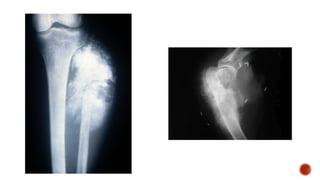

Osteosarcoma osteolítico

 Es una neoplasia indiferenciada, existe un incremento de osteoclastos, que son las

que proliferan produciendo destrucción y necrosis ósea.

 Radiologicamente se usa el término osteolítico para señalar un segmento óseo que

muestra ausencia de tejido calcificado u osificado, que se identifica como un defecto

en el tejido que conforma el hueso.

 histopatologicamente, se señala la existencia o no de tejido óseo en cualquiera fase

de su evolución osteoblástica.

Osteosarcoma osteolítico  Esuna neoplasia indiferenciada, existe un incremento de osteoclastos, que son las que proliferan produciendo destrucción y necrosis ósea.  Radiologicamente se usa el término osteolítico para señalar un segmento óseo que muestra ausencia de tejido calcificado u osificado, que se identifica como un defecto en el tejido que conforma el hueso.  histopatologicamente, se señala la existencia o no de tejido óseo en cualquiera fase de su evolución osteoblástica.